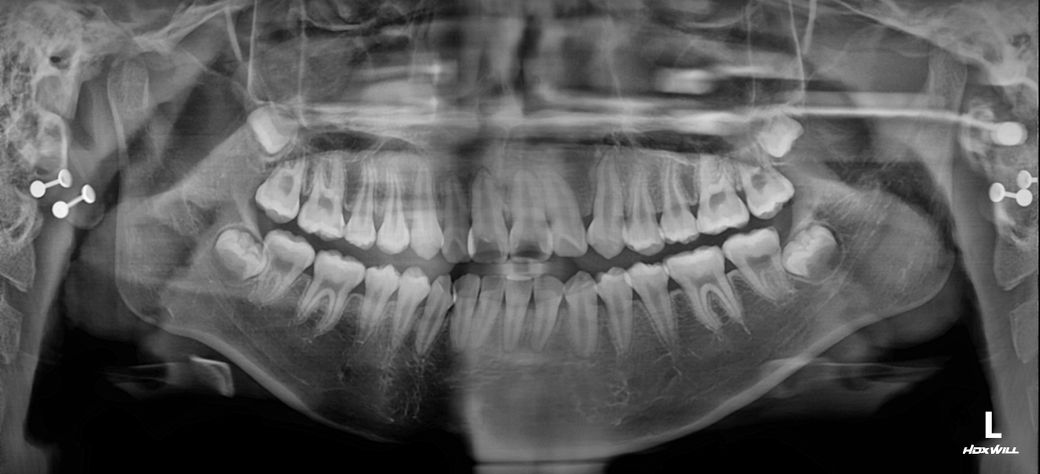

중1 여자 아이 교정진단 부탁드립니다.

앵글씨 몇급인지 궁금합니다.

의사 선생님마다 소견이 다르셔서 혼란 스럽네요.중1 여자 아이구요.시기적으로 지금 교정을 시작하기에 적절한지 궁금합니다.

• 2번 째 사진

앵글 2급 부정교합이며, 지금 교정하는 것이 좋을 것으로 보입니다. 더 늦어지면 교정이 까다로워 질 수도 있습니다. 지금 현재도 쉬운 케이스는 아닙니다.

앵글씨 부정교합측면에서 보면 1급인거 같고 치열이 좋지 않아서 중학교 1학년이면 교정을 시작하셔도 괜찮을 시기인거 같습니다.